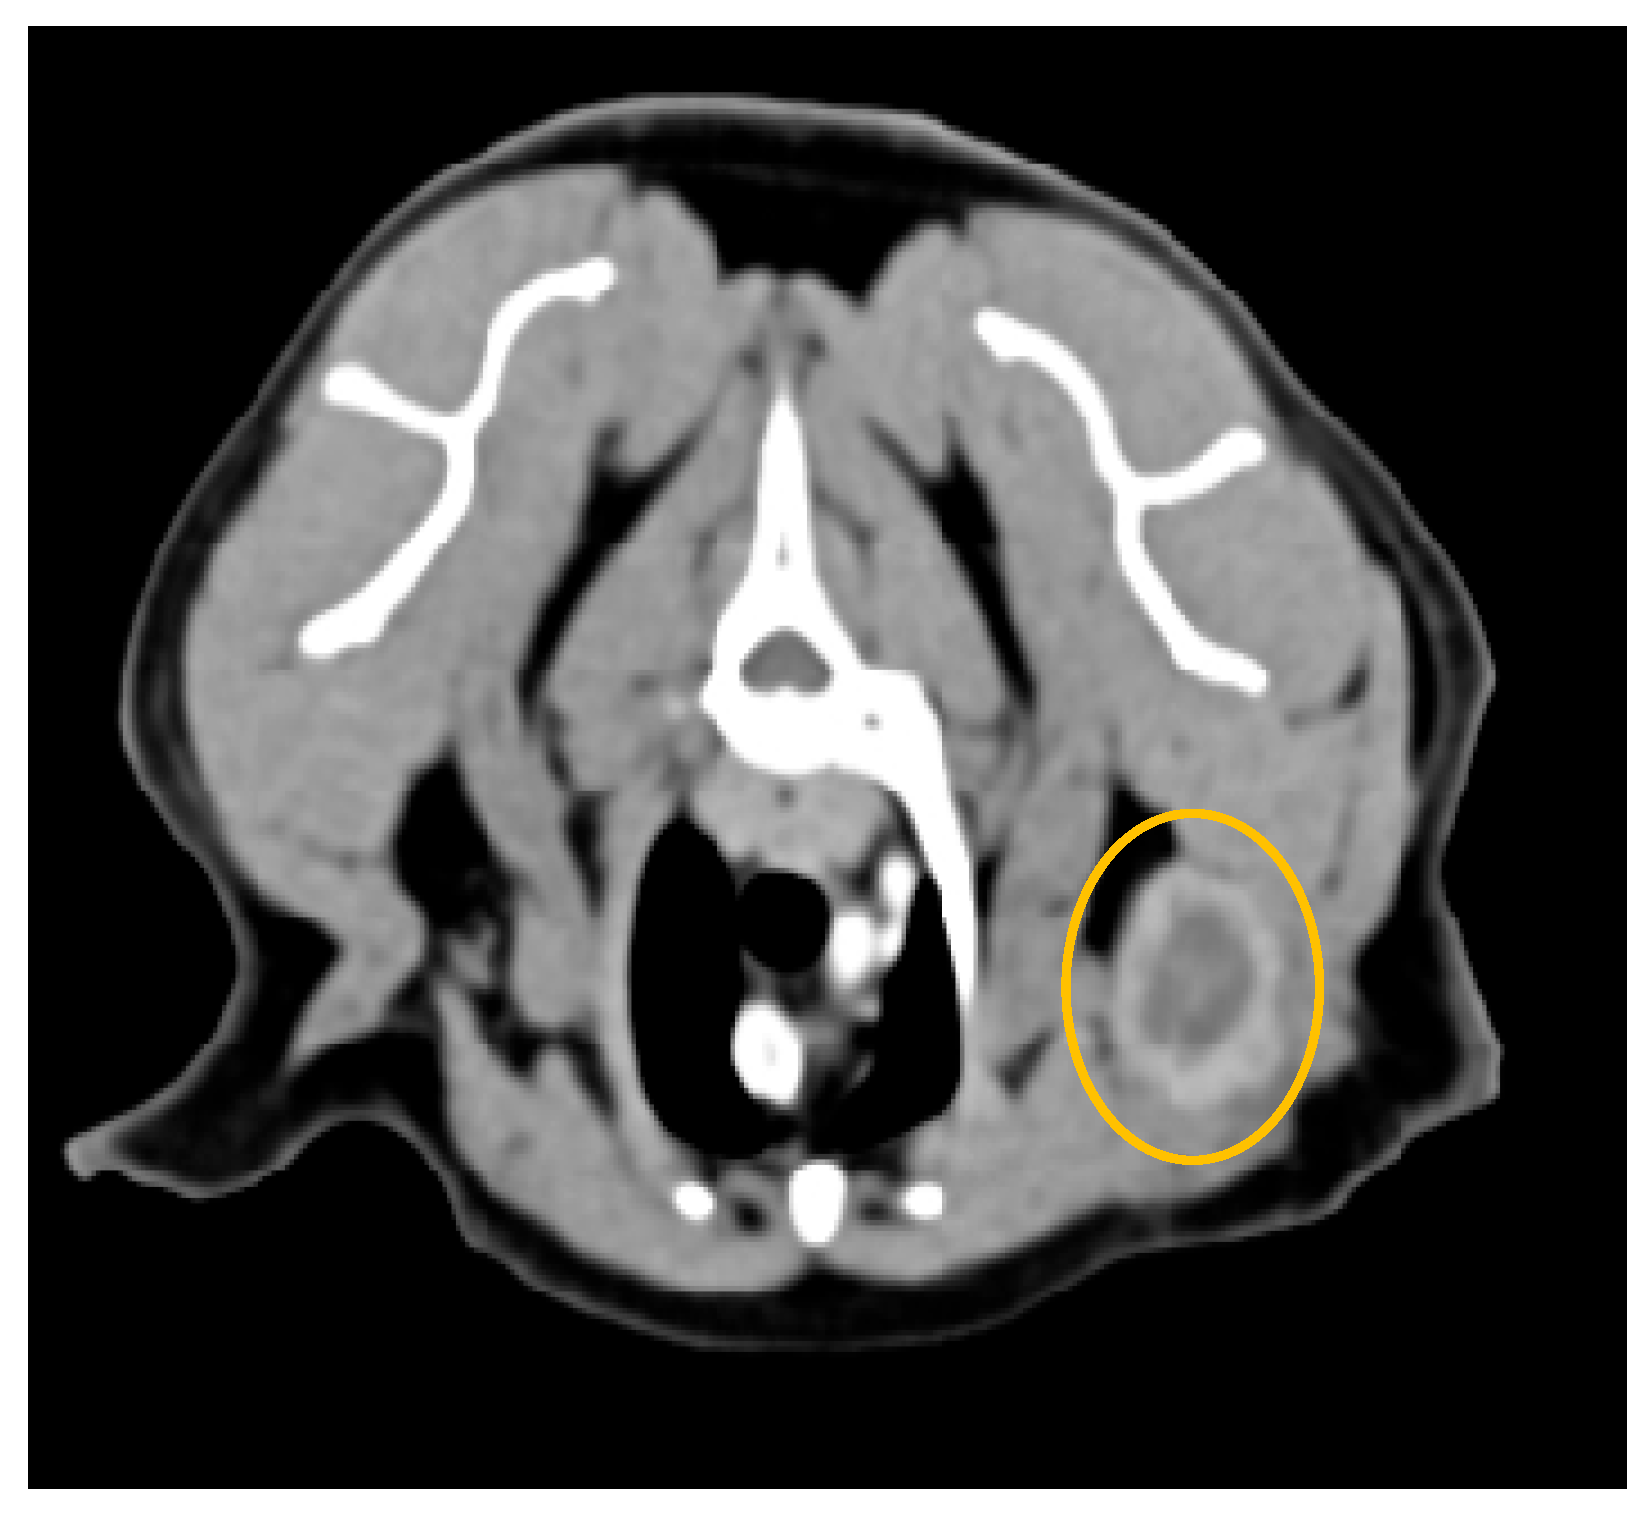

3.2. Computed Tomography